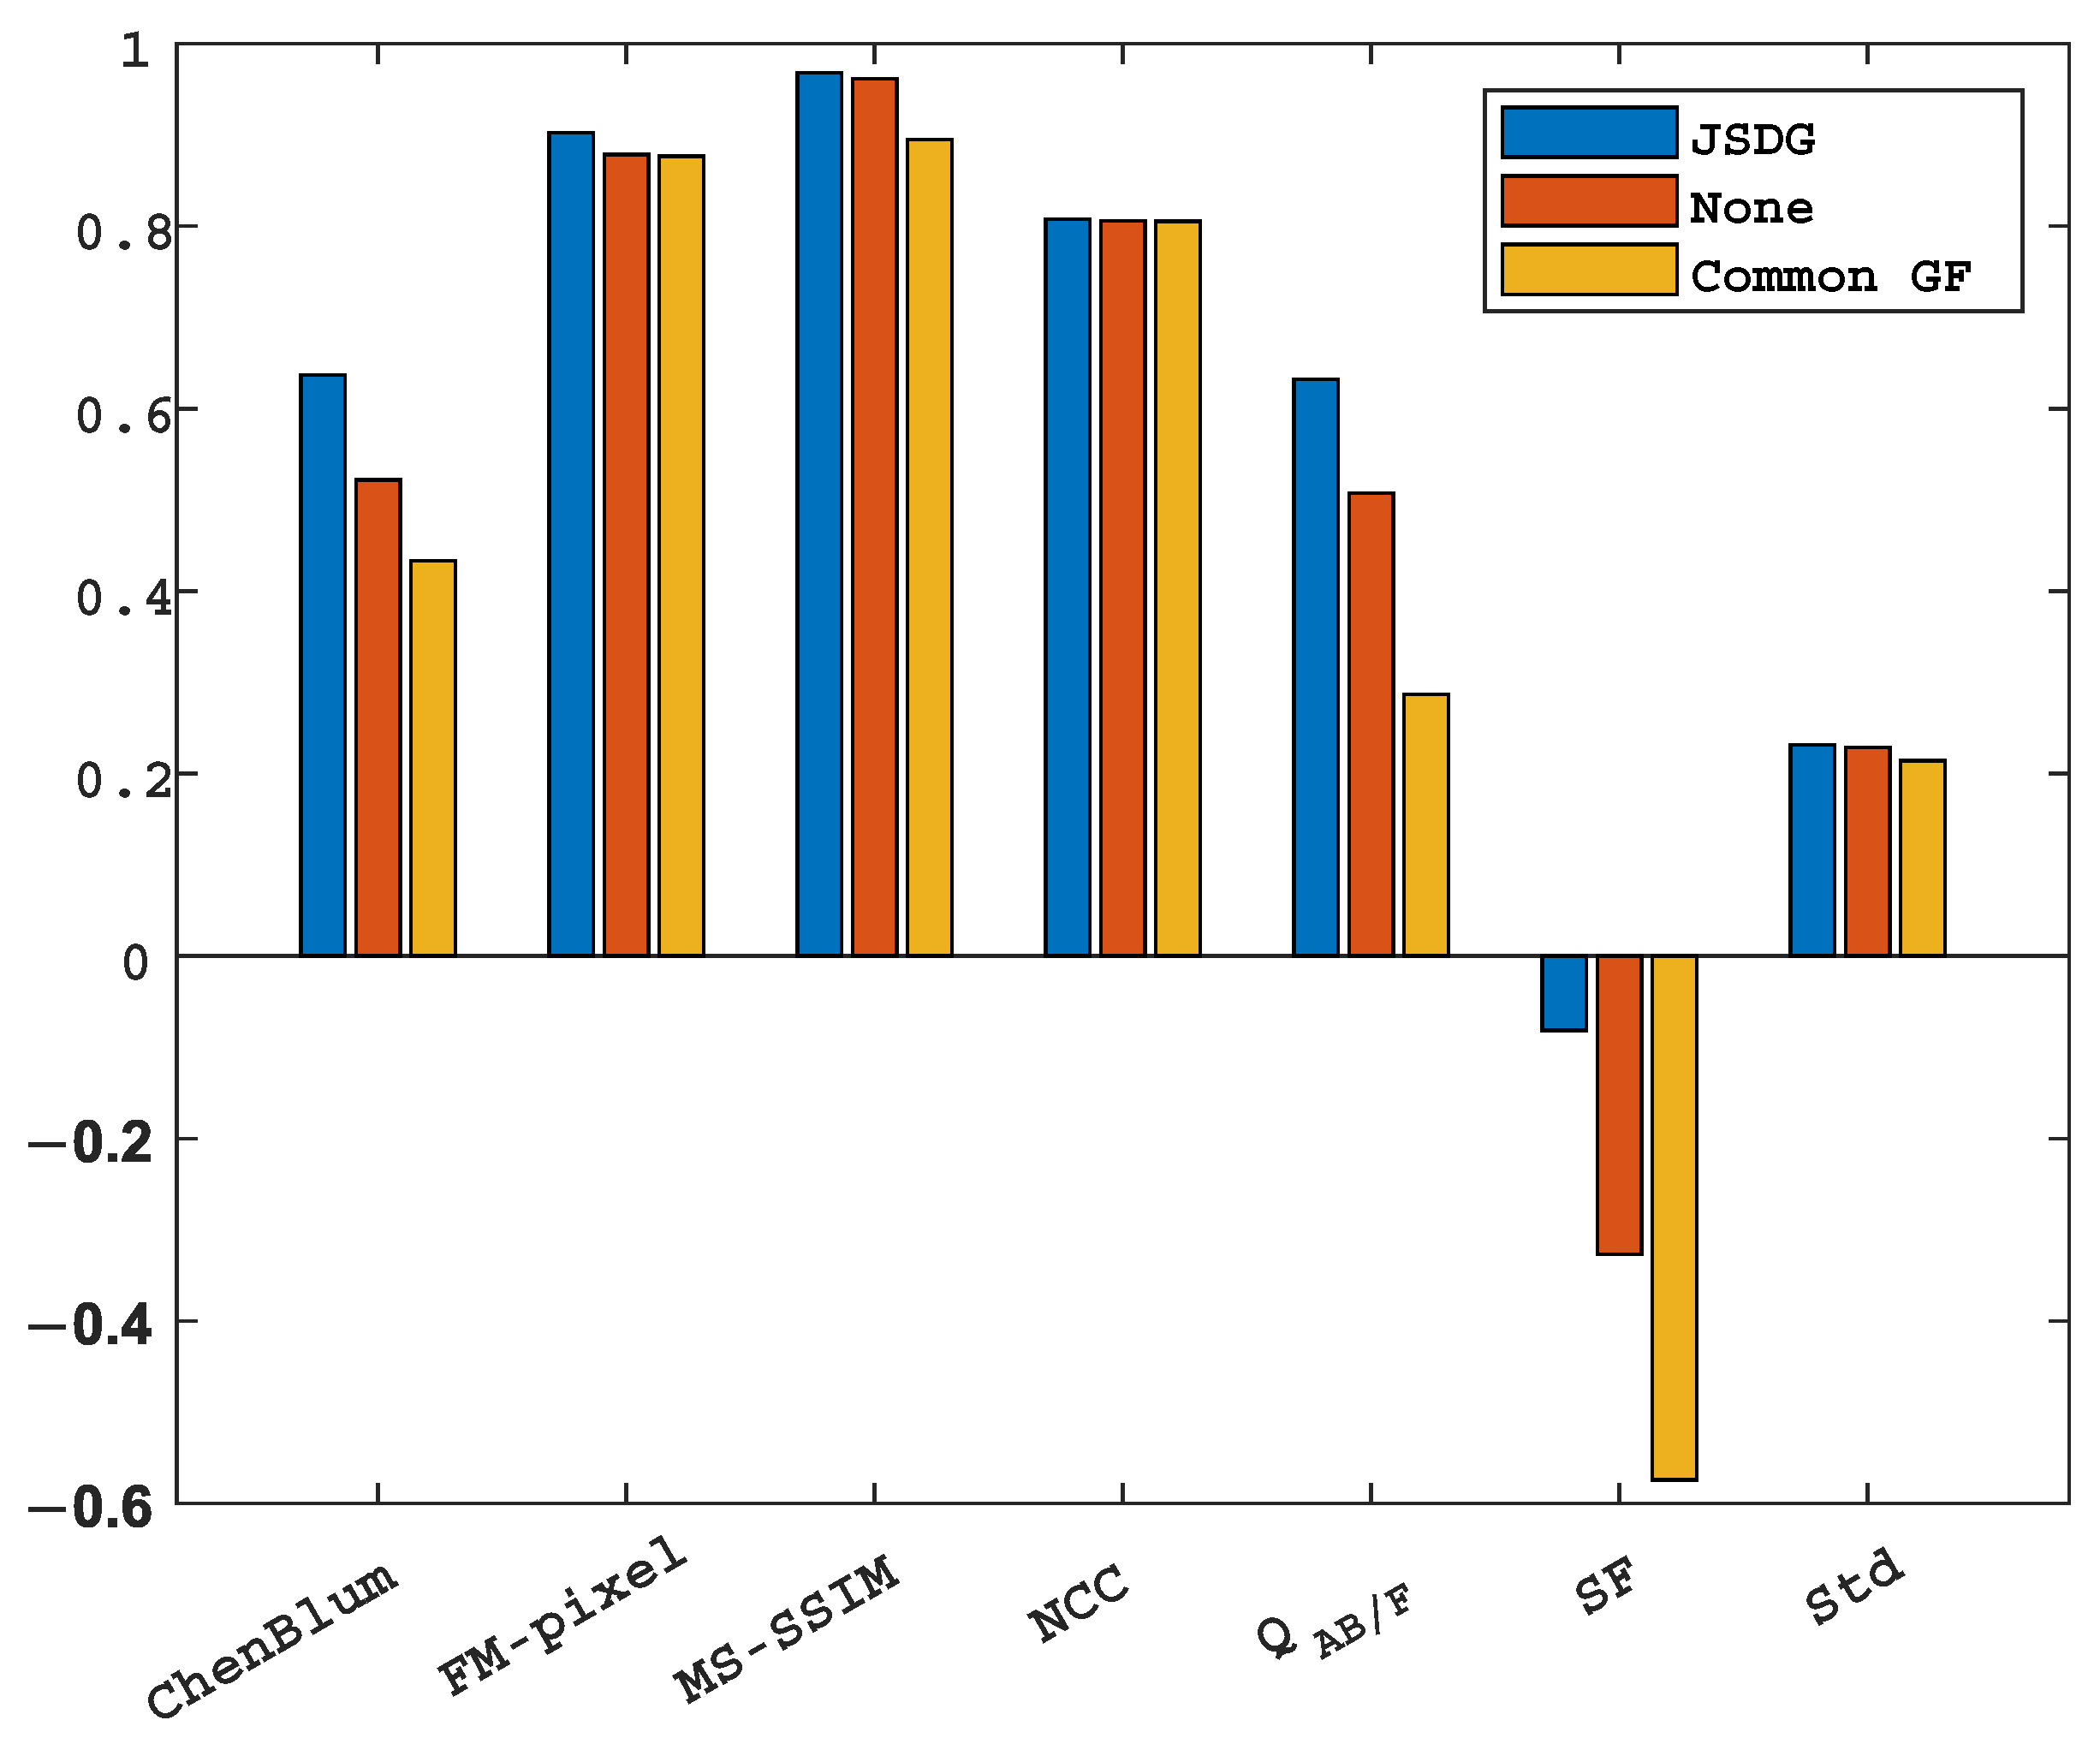

5.4.3. Ablation Analysis